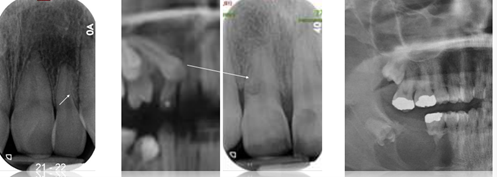

19

common presenting factors for external inflammatory resorption

A

restoration encroaching on pulp PA and resorption mesial root, trauma

PA radiolucency, apex nibbled away, incisor has bad endo inflammation grown to overlap canine

* need to remove inflammation source to solve (endo canine wont solve alone)

Q

aetiology of external inflammatory resorption

The pulp is necrotic - bacterial or dental trauma in origin

The periapical inflammatory lesion precipitates the resorption process

In actual fact the majority (81%) of teeth with periapical lesions will have microscope areas of root resorption

* Only 7% of these are detectable radiographically